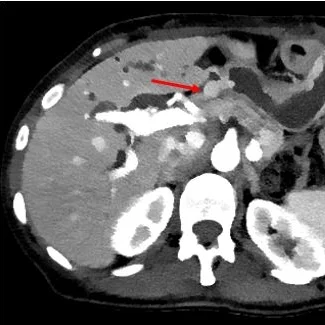

Conventional CT (axial plane): Do you see the gastric antral submucosal nodule?